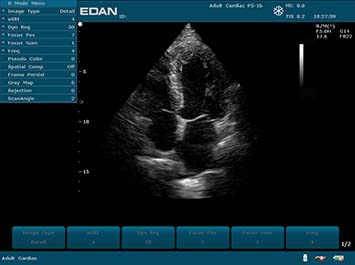

Клинические изображения